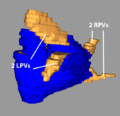

- Carma 3RPV.png 600 × 555; 148 KB

- Carma 3RPVs.png 600 × 555; 148 KB

- Carma Norm RPVs.png 593 × 551; 115 KB